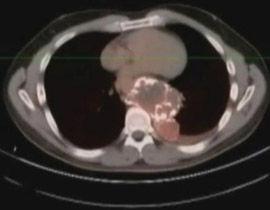

صورة X-Ray للورم السرطاني! |

وقال أبكن "ظننت أنني أشكو من تمزق عضلي لكن الطبيب تجهم ما أن نظر إلى الشاشة التي تكشف ما في داخلي". وأضاف "لم يعرفوا ما الذي ينمو في البداية"، مضيفا انه تبين لاحقا انه ورم صلب بحجم كرة قدم ولديه تشعبات.

وقال الأطباء للرجل أن الورم بات عملاقا وأخذ يضغط على قلبه ورئتيه وأمعائه، وأوضحوا له ان الورم ينمو على ما يبدو منذ قرابة العقد.

وأخضع أبكن لجراحــــة استؤصل فيها الـــورم واضطـــر بعد ذلك للخضـــوع لجراحـــة ترميـــم استغرقت عدة ساعات. وقال د.دي بيرنا ان "محاولة استئصال ورم كبير ومتكلس وصلب كالصخرة كانت تجربة طبية صعبة"، وسيجري أبكن صورا مقطعية مستمرة للتأكد من عدم عودة الورم.